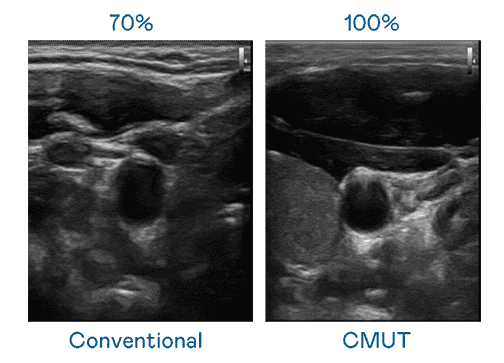

CMUT 技术是一种用电容式微机电元件来产生超音波讯号的技术。。与传统 PZT 压电式技术相比,,,CMUT 频宽增加 30%,,,,更宽频的超音波讯号让影像解析度大幅提升,,,,是实现高影像品质医疗超音波扫描、、促进精准医疗发展的关键技术。。。

大频宽带来超清晰影像

超音波影像的解析度高低,,首先取决于探头能发出的讯号频宽。。牛牛游戏 CMUT 可提供高清晰的超音波讯号,,,,提供高频宽、、、高灵敏度、、影像纹理细节更高的超音波影像,,协助医护人员缩短影像判读时间及利用精准的医疗影像进行诊断。。。